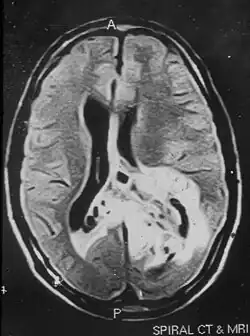

Papilläre glioneuronale Tumoren sind sehr selten. Sie treten über einen weiten Altersbereich hin auf, wobei das mittlere Alter bei Diagnosestellung 27 Jahre beträgt. Die Tumoren sind typischerweise im Bereich der Temporallappens lokalisiert. In der Kernspintomographie stellen sich glioneuronale papilläre glioneuronale Tumoren als gut abgegrenzte Raumforderungen mit Kontrastmittelaufnahme dar.